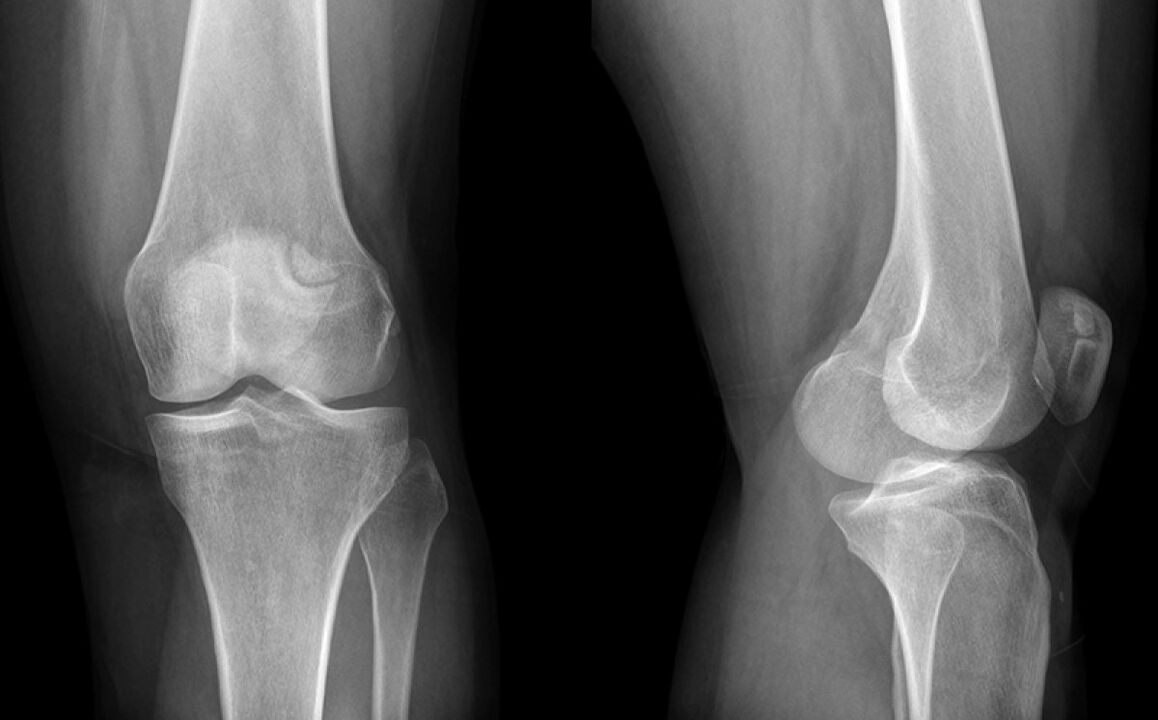

Il ginocchio ha fatto male tre settimane. Alla fine, sono andato da un medico che sospettava il danno al menisco e mandato a un raggio X. La diagnosi è lo stadio iniziale dell'artrosi dell'articolazione del ginocchio.